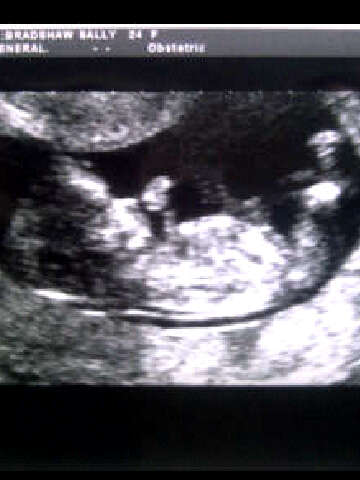

Please could anyone guess based on skull as there's no nub Attachment 6798

Boy skull (must be taken with a grain of salt!)